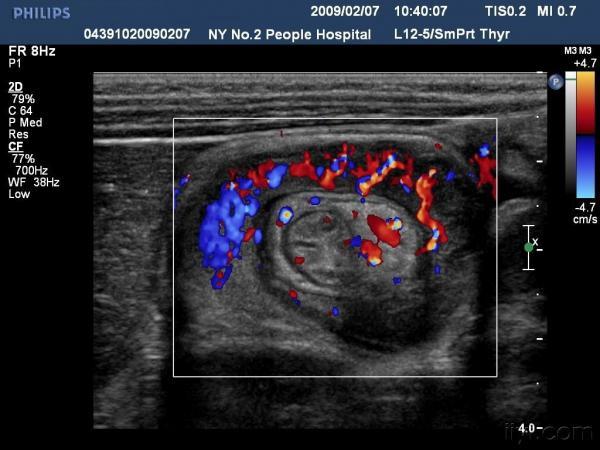

【贴图】肠套叠

患儿哭闹数小时来我院就诊,超声检查发现右侧相当于结肠肝区位置可见“同心圆征”。来和大家分享一下,呵呵。